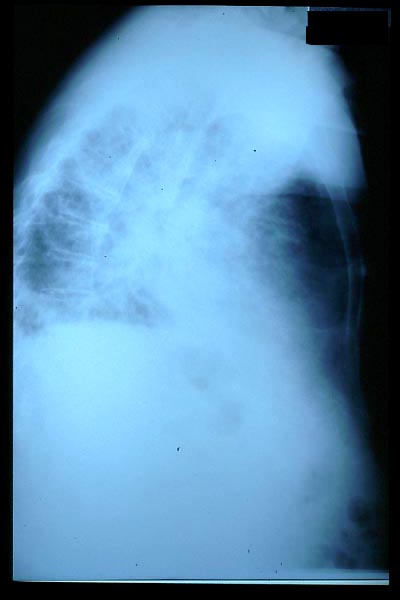

Osteoporosis. Cifosis.